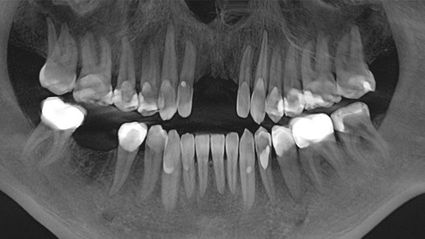

Mein erster Besuch war im Dezember 16. Ich ließ meine 4 Weisheitszähne reinigen, 3 weitere Kavitäten (von Zähnen, die im Sommer 16 in den USA gezogen worden waren) reinigen und Implantate einsetzen. Außerdem wurde eine Goldkrone und ein wenig Metall entfernt. Bei meinem letzten Besuch am 16. Juli haben wir verschiedene Zähne mit Kunststofffüllungen repariert und durch Keramikfüllungen und Kronen ersetzt. Vor allem aber zogen wir 2 Zähne, die tiefe Wurzelinfektionen aufwiesen, reinigten Karies und setzten 2 Implantate ein. Ich spürte fast sofort einen Seufzer der Erleichterung in meinem ganzen Körper. Dann ein Energieschub! Hier wird alles daran gesetzt, dass der Patient vor, während und nach dem Eingriff die besten Chancen auf Heilung und Genesung hat.